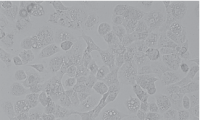

细胞名称: BIU-87人膀胱癌细胞

细胞形态: 上皮细胞样

生长特性: 贴壁生长

BIU-87建系于1989年,该细胞系来源于人膀胱乳头状移行上皮癌,通常采用5×108细胞0.2mL接种裸鼠皮下,呈进行性肿瘤生长,肿瘤结节病检与原标本癌组织相似。22代细胞群体倍增时间为34小时。细胞能在软琼脂上生长,克隆形成率23%。BIU-87细胞系对ConA,WGA,PSL均有凝集反应。